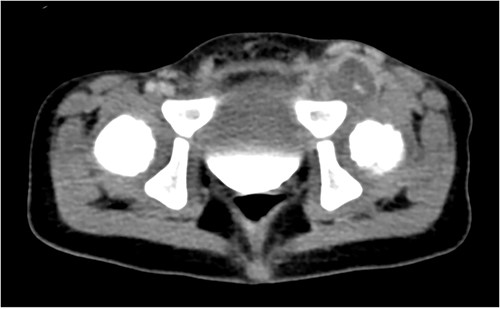

The patient became progressively non-weight bearing on the left LE and developed significant pain with hip adduction. An ultrasound Doppler demonstrated complete occlusion of the left common femoral artery with a thrombosed aneurysm and reconstitution of flow to the popliteal artery. CT angiographydemonstrated complete occlusion of the left common femoral artery (Fig. 1). He had weak dorsalis pedis pulses and biphasic signals in the ipsilateral dorsalis pedis and posterior tibial arteries. Due to persistent thrombosis on anticoagulation, loss of palpable pulses and change in Doppler signals, he was taken to the operating room. Preoperative vein mapping revealed an inadequate greater saphenous vein diameter (1 mm), and an absent right internal jugular vein (ligated after previous ECMO cannulation). The procedure began with a left retroperitoneal incision to obtain proximal control of the ipsilateral common, internal and external iliac vessels and a left groin incision to expose the femoral aneurysm. There was an extremely dense inflammatory response that obliterated a significant segment of common femoral vein with purulent material extruding from the region (Fig. 2A). The 2 mm profunda artery was the remaining outflow. A 6 mm cryopreserved cadaveric artery allograft (CryoArtery©) was utilized to perform the bypass between the external iliac artery and the profunda femoris artery in an end-to-side fashion using interrupted 5–0 Prolene® suture. The wound was closed in three layers using absorbable suture. The mycotic aneurysm was resected from the external iliac artery to the proximal superficial femoral artery. As the femoral vein was densely adherent to the inflammatory mass, a segment was removed and reconstructed with CryoArtery© (Fig. 2B). Inflammatory markers (preoperative C reactive protein 24 mg/l and procalcitonin 21 ng/ml) downtrended postoperatively (1.5 mg/l and 0.13, respectively at discharge). The patient was discharged 48 days postoperatively. Serial fungal tests were followed, and antifungal coverage was discontinued 1 year after discharge. As of 36 months follow-up, the patient is ambulating well with equal pulses and no evidence of limb-length discrepancy.

Axial computed tomography showing a large left common femoral artery mycotic aneurysm with a dense inflammatory reaction.